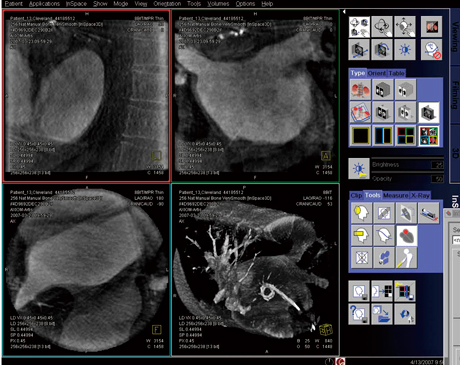

冠動脈をとらえた2方向の撮影画像から,立体的な冠動脈画像を構築する3Dアプリケーションで,従来搭載していた“syngo IC3D”の後継アプリケーションである。血管径や,狭窄度・分岐角度・病変長などを正確に測定できる機能はもちろんのこと,オートモードのみであった血管辺縁のトレースをマニュアルで修正する機能を追加することで,PCI治療計画時の応用範囲を広げている(図5)。

図5 syngo IZ3D